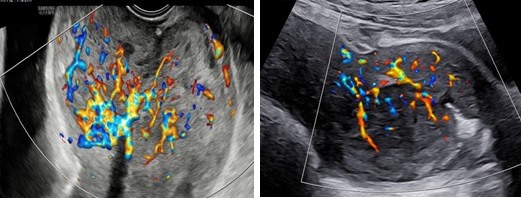

Siêu âm: Tử cung ngã trước, kích thước: 56 x 62 x 90 mm. Cơ tử cung mật độ đều, đồng nhất. Từ thành trước đoạn thân nhô vào lòng tử cung kéo dài tới cổ tử cung có khối echo dày không đồng nhất kích thước 64 x 81 x 70 mm, không rõ ranh giới với cổ tử cung và cơ tử cung. Trên Doppler màu khối tổn thương phần ở lòng tăng sinh mạch máu độ 2 và ở vùng cổ tử cung độ 4.

Hình 3: (trái: ngã âm đạo, phải: ngã bụng): Trên Dopple màu, phần tổn thương ở cổ tăng sinh mạch máu độ 4, không ranh giới giữa tổn thương và cơ vùng cổ tử cung